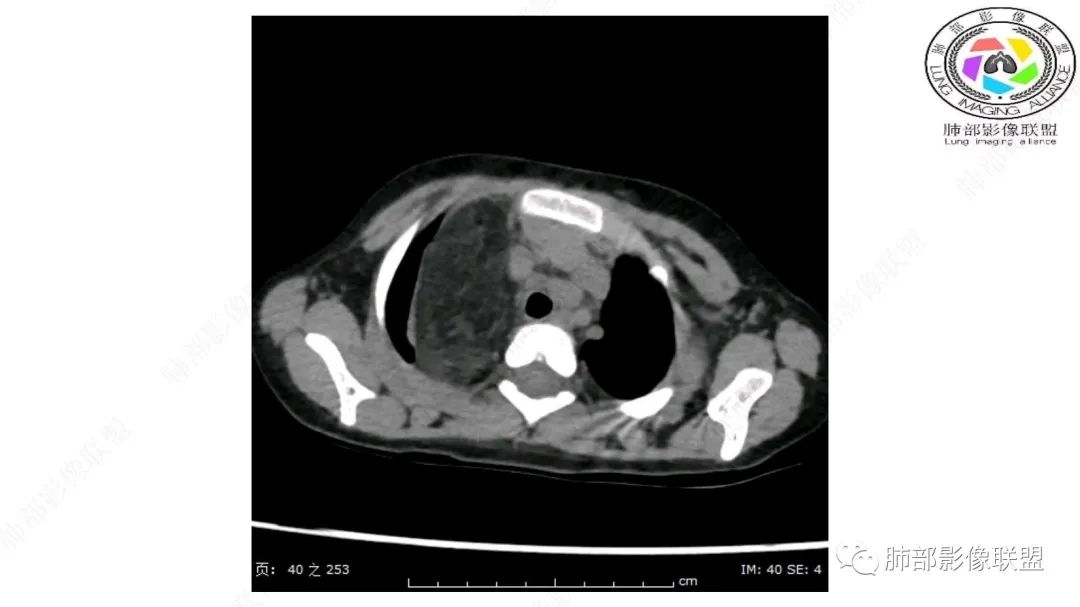

右上纵隔混杂密度肿块,边缘光整,与纵隔分界清,其内多发脂肪密度,增强无明显强化,其内血管穿行,考虑纵隔脂肪母细胞瘤,鉴别畸胎瘤,脂肪肉瘤。

病灶属于交界区,主体位于肺内,占位效应明显,前方突入胸壁,胸腺受压变形,胸膜显示欠清楚;病灶包绕上叶肺动脉;似乎有体动脉供血。符合肺内的点:包绕上叶肺动脉分支;符合纵隔的点:前方似乎突入胸壁,与胸腺关系比较密切,但是与上腔静脉的关系提示病灶不支持纵隔来源,前纵隔的常规会将上腔静脉受压后移、外移,这是不符合的。

手术记录:见右肺上叶肿物,肿物与右肺上叶关系密切。与纵隔无粘连,逐步分离肿物,见肿物大小约6cm*5cm,边界清楚,于右肺上叶粘连,边界清楚,肿物包绕右肺上叶血管及支气管。超声刀逐步游离肿物,完整切除肿物,右肺上叶肺组织无破溃,表面无出血。

1.右上肺-纵隔交界区巨块影,主体位于右肺一侧,紧贴胸腺、头臂干、右锁骨下动脉、上腔静脉、奇静脉等,不能分离,但病灶整体边界清楚。注意上述相邻腔静脉等结构未见受压变形,纵隔亦未见明显向左推移,至少提示两点:

2.肺动脉穿行也许是肺内来源最重要支持点!